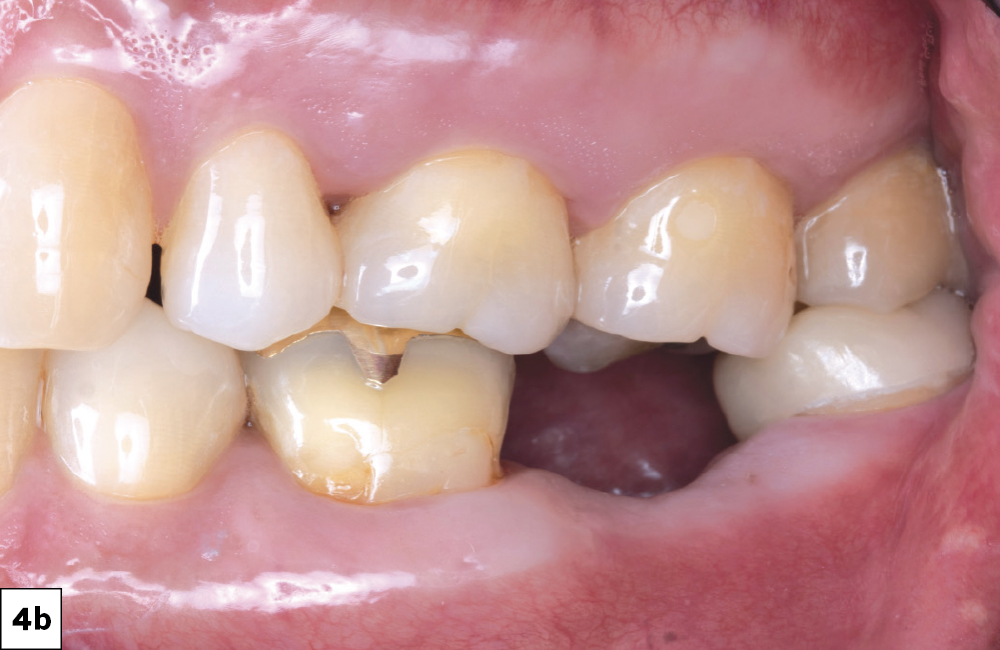

In-office milling is a quickly evolving option for the modern dental practice. With the introduction of a same-day screw-retained option, BruxZir® NOW SRC milling blocks, there’s even more opportunity for optimizing single-unit restoration workflows. In this case study, I’ll demonstrate how this product can be used as part of an efficient workflow for tooth replacement in the posterior. When combined with guided surgery and in-office crown design, this procedure offers reliable results while saving money and significantly cutting down on chair time for dentists.